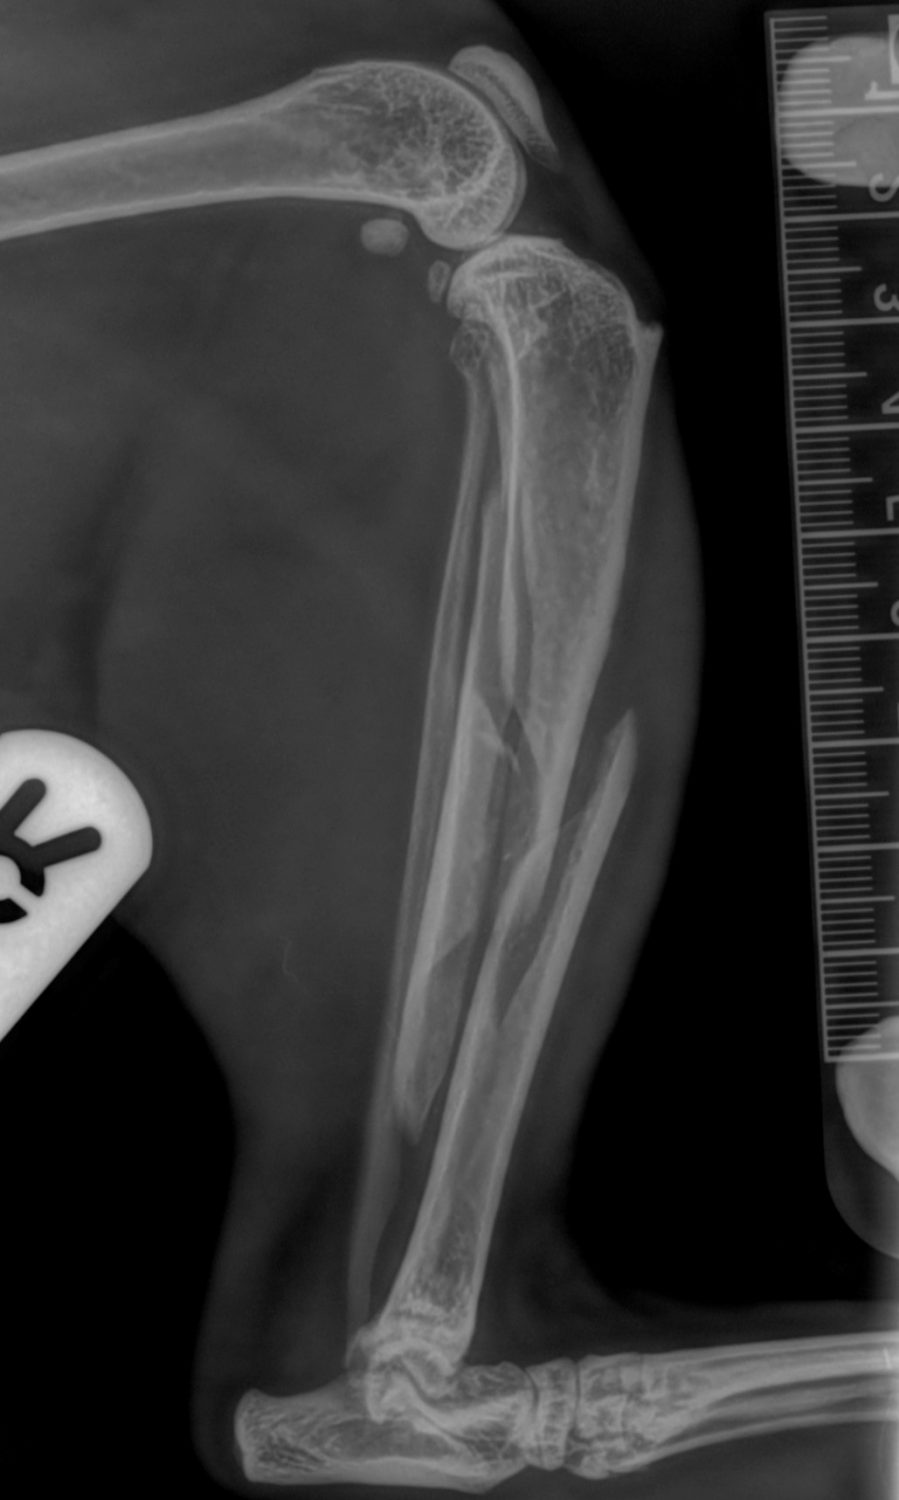

Tilly is a 10 year old cat who went missing for 3 days, returning unable to use his right back leg. He was initially seen by Sevenoaks Head Vet, Penny.  She could feel a fracture in his lower leg. Following an anaesthetic and x-rays a tibial fracture was confirmed. A treatment plan was made and his owners consented to surgery.

Before and after radiographs can be found within the carousel below along with intra-operative photographs.